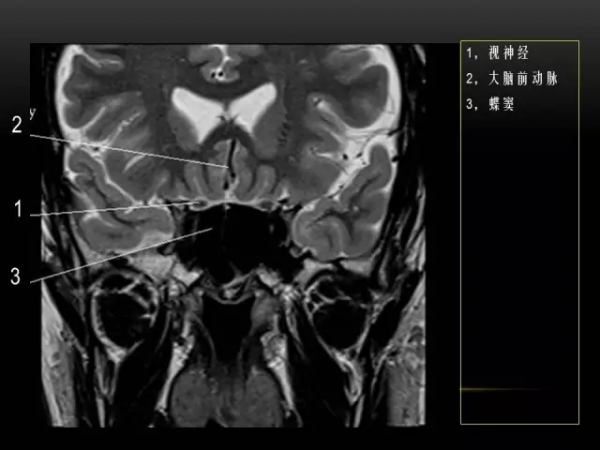

MRI下眼部及鼻竇的冠狀位解剖